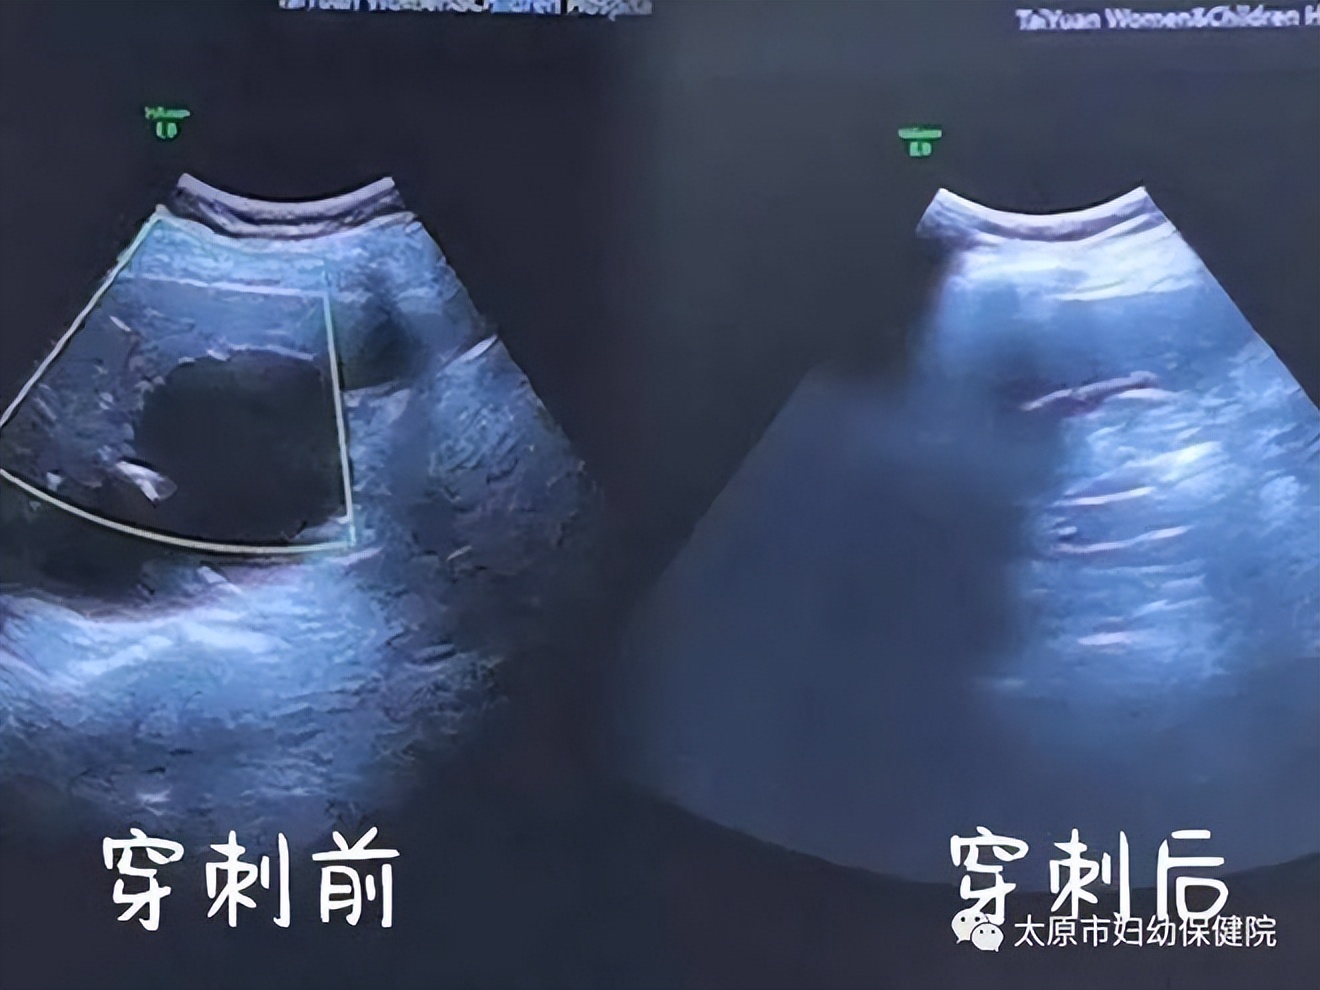

通过上腹部彩超发现成阿姨肝部有一个较大的囊肿,尺寸达8cm×6cm,压迫了周围组织结构,引起上腹部不适症状,如果不及时处理,还可能出现囊肿进行性增大,遇外力挤压导致破裂出血,甚至可能会危及生命。

手术中,经超声精确定位,局部麻醉,两位有丰富介入与穿刺经验的专家熟练操作,不到半个小时便顺利抽出约50ml囊液,将囊液抽吸干净后,使用聚桂醇液注入囊腔内,保留的囊肿内聚桂醇液可对囊肿内壁细胞达到缓慢破坏,使得囊壁内皮细胞不再分泌液体,达到治疗目的。

这种超声引导下介入新疗法准确性高,不仅创伤小、患者痛苦少,而且手术时间短。经过治疗后的成阿姨达到了预期的手术效果,一根小针就驱散了困扰她多日的阴霾。